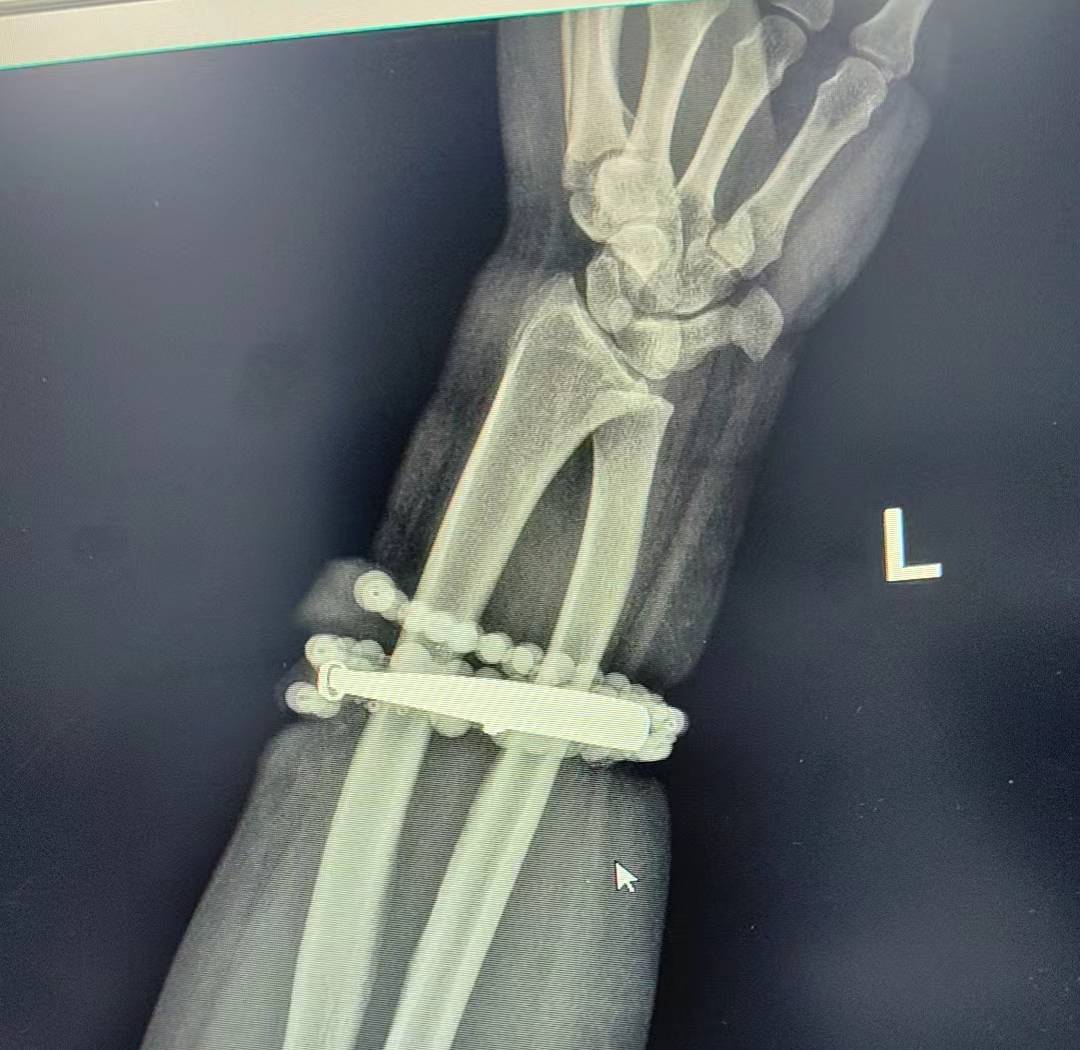

經過一個(ge)多小時的(de)手(shou)術,醫生們將手(shou)鐲和串珠從厚厚的(de)增(zeng)生組織中完(wan)整剝離出來(lai)。目(mu)前,龔女士恢復(fu)良好,已順利出院。